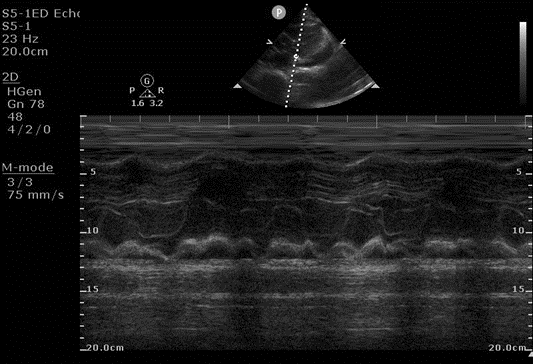

The ED physician then performed two measurements. First, they obtained a parasternal long axis view and placed an M-mode line through the right ventricular free wall and the mitral valve (Figure 1), showing diastolic collapse of the right ventricle.

Figure 1. M-mode image of right ventricular diastolic collapse, occurring when the mitral valve is open.

The use of M-mode in Figure 1 is an easy way to distinguish whether the right ventricle wall collapses during diastole, as the opening of the mitral valve is easily visualized on M-mode as the start of diastole. Other ways to determine diastole would be to slow playback speed on the machine when reviewing the clips, or to use cardiac leads to determine systole (QRS) versus diastole (T wave).